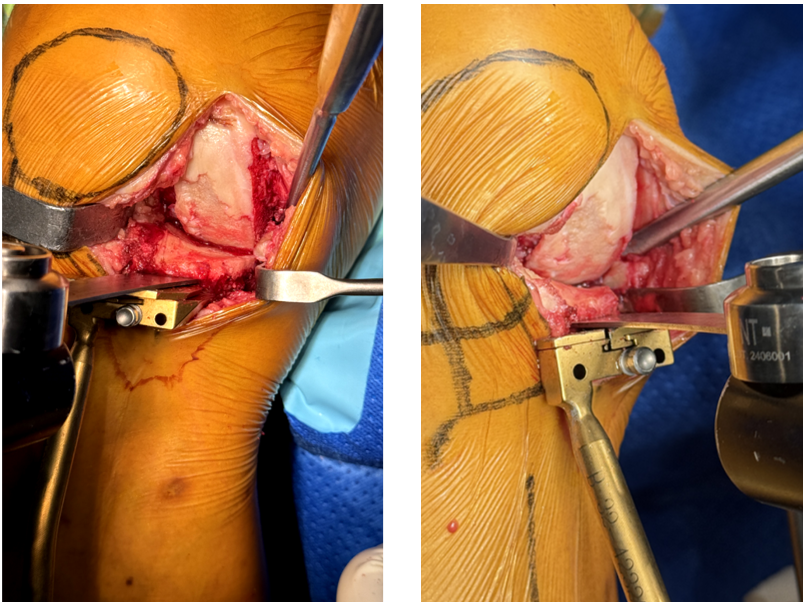

6、安装股骨远端截骨导板

-

膝关节完全伸直,试插合适屈曲/伸直间隙间隔块厚端,其下面与胫骨截骨面齐平,上面与股骨髁远端接触,用电灼通过其上面在股骨髁上划线(股骨远端预截线);

根据实测屈伸间隙大小,算出股骨远端截骨量,选择合适型号的股骨远端截骨导板/下方插片,插入间隙,1枚带螺纹钉牢固固定。

8、安装股骨二合一截骨器

屈曲膝关节,将合适的二合一截骨器紧贴股骨远端截骨面,导板紧贴股骨后髁,1枚有头螺纹钉拧入顶部固定孔中,旋转导向器,直到导板与胫骨的截骨面平行;

1枚有头螺钉拧入前倾固定孔中,1个短头固定螺钉拧入最靠近髁间的中间孔内中。